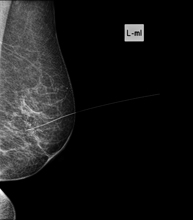

Mamografia

Els estudis de Mamografia obtenen imatges generades a partir de raigs X de dosi molt baixa que permeten detectar les diverses patologies dels teixits mamaris (en especial el càncer de mama), tant per al cribratge (screening) ginecològic com per al diagnòstic dirigit. La mamografia pot ser intervencionista amb punció de quists, biòpsia estereotàxica, marcatge prequirúrgic i galactografia.

Mamografia digitalitzada

La mamografia digitalitzada és una tècnica innovadora que permet estudiar la mama amb un dosi baixa de radiació, que és més reduïda que la mamografia convencional. La imatge es digitalitza a partir d'uns bastidors especials, anomenats CR. Gràcies a aquestes tècniques de digitalització s'obtenen imatges excel·lents, sobretot en mames de difícil estudi com les glàndules que es presenten en la mamografia com una mama densa, i permet detectar millor en aquest grup de pacients les tumoracions.